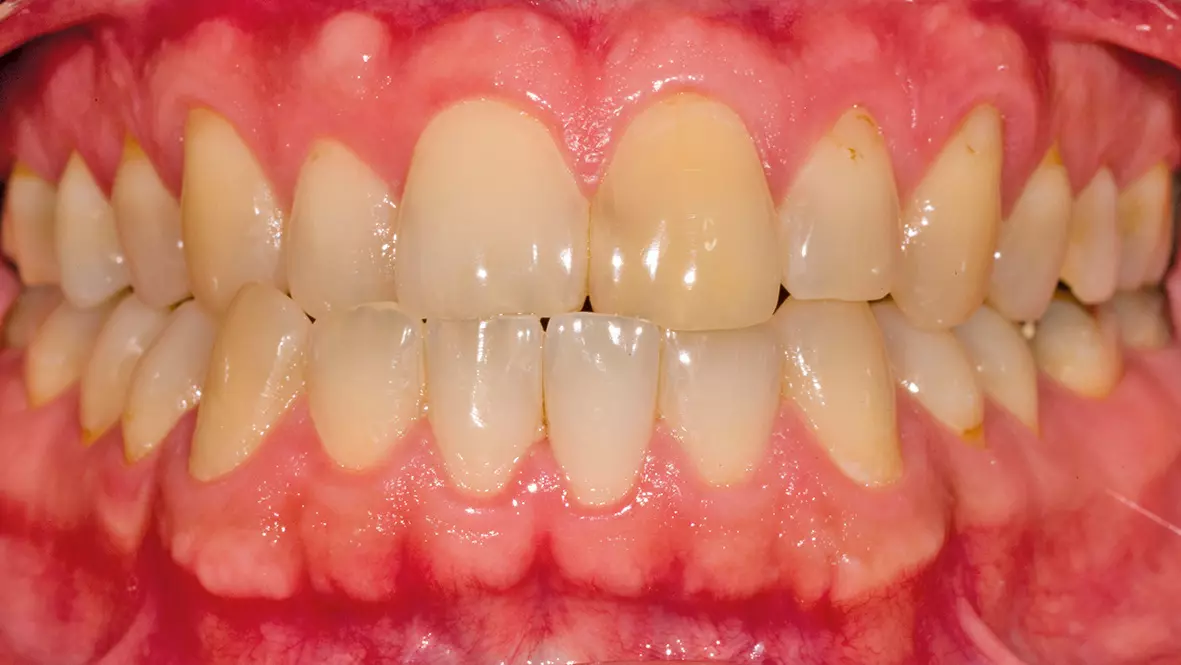

Nach der Extraktion eines Zahnes geht im Verlauf der Wundheilung in wenigen Tagen die Anatomie der Alveole und des Sulkus verloren. Ohne räumliche Orientierung ist es später während der Implantatversorgung schwierig, diese wiederherzustellen. Unter Verwendung des extrahierten Zahnes kann die Krone in der korrekten Form gestaltet werden (Abb. 1 bis 3).

Bei dem Patienten wurde bei Zahn 11 eine Querfraktur festgestellt. Leider konnte der Zahn nicht mit konservierenden Maßnahmen erhalten werden und es stand eine Extraktion an. Das weitere Vorgehen wurde mit dem Zahntechnischen Labor abgesprochen. Mit Hilfe der Situationsmodelle konnte zunächst ein Provisorium erstellt werden. Nach der Extraktion des Zahnes wurde die Socket Preservation Technik unter Verwendung von Bio-Oss® Collagen von Geistlich Biomaterials und einem Schleimhauttransplantat vom Gaumen angewandt. Es konnte eine provisorische Schiene zum Ersatz von Zahn 11 eingesetzt werden (Abb. 4).

Durch den Aufbau des räumlich korrekten Knochenvolumens konnte bei der Implantatplatzierung die ursprüngliche Situation wiederhergestellt werden. Als „Wax-up“ diente der extrahierte Zahn (Abb. 11). So konnte jetzt entweder gleich die definitive Krone oder eine provisorische Krone hergestellt werden. Wir entschieden uns für die Herstellung einer provisorischen Krone, um die Reaktion der Gingiva auf die Implantatkrone zu beobachten und gegebenenfalls noch darauf reagieren zu können (Abb. 12 bis 14).